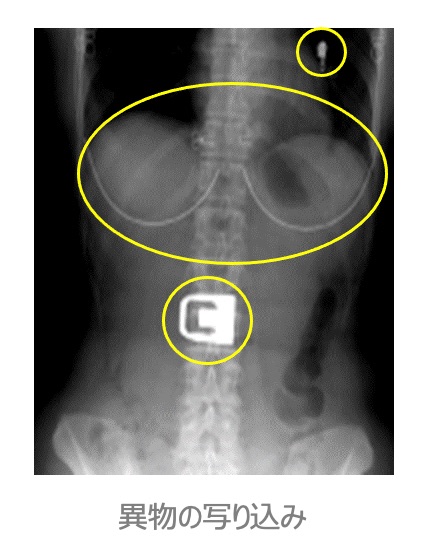

●ご注意頂きたいこと

- 貴⾦属(ネックレス、ピアスなど)

- ⼊れ⻭、眼鏡

- ブラジャー(⾦属の⼊ったもの)

- ズボンのベルト、ファスナー

- 湿布、カイロ、エレキバン

- プラスチック類(下着のアジャスター、ボタンなど)